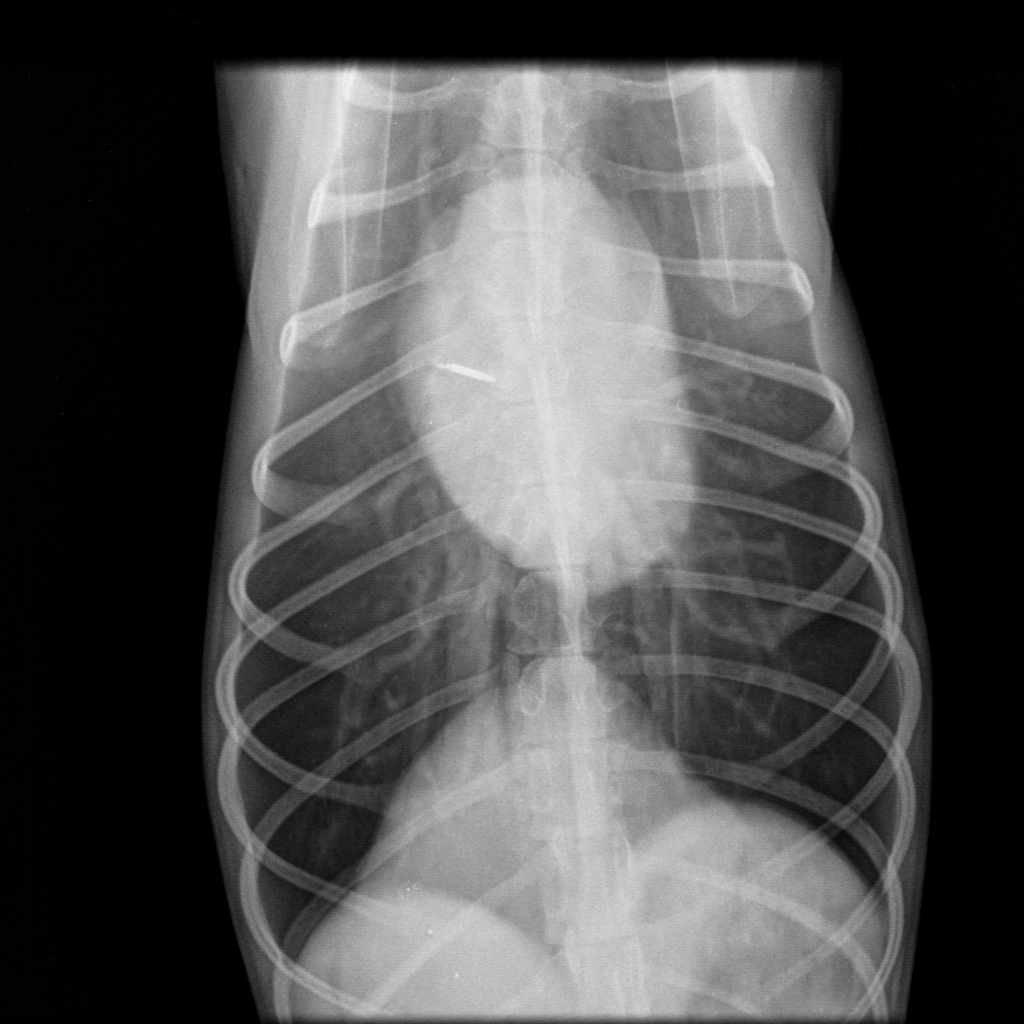

Отделение рентгенодиагностики оборудовано современной системой получения рентгеновских снимков и позволяет получать изображения грудной клетки в высоком разрешении (сердце, сосуды, легкие, трахея и др.). Это позволяет заметить даже незначительные изменения размеров сердца, новообразования маленьких размеров, верно оценить структуру тканей.